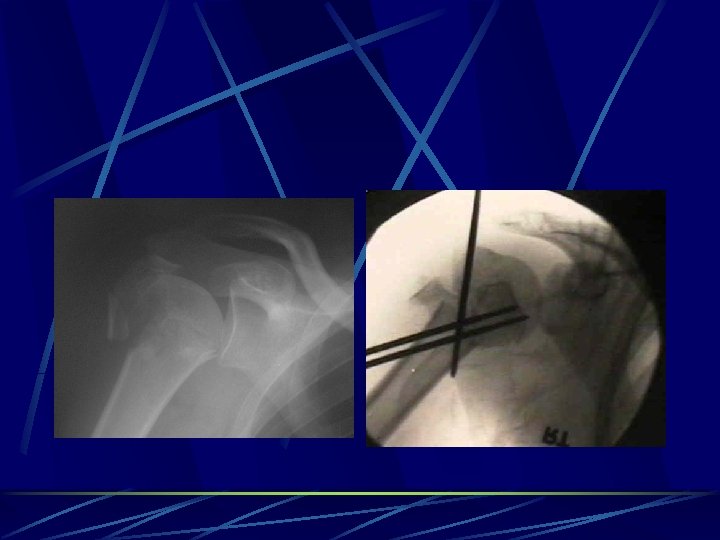

Kirschner wires commonly used in fractures around joints. resist only changes in alignment, they do not resist rotation and have poor resistance to torque and bending forces used as adjunctive fixation for screws or plates and screws casting or splinting is used in conjunction. can be placed percutaneously adequate for small fragments in metaphyseal and epiphyseal regions, especially in fractures of the distal foot, wrist, and hand, ( Colles fractures, and in displaced metacarpal and phalangeal fractures after closed reduction )